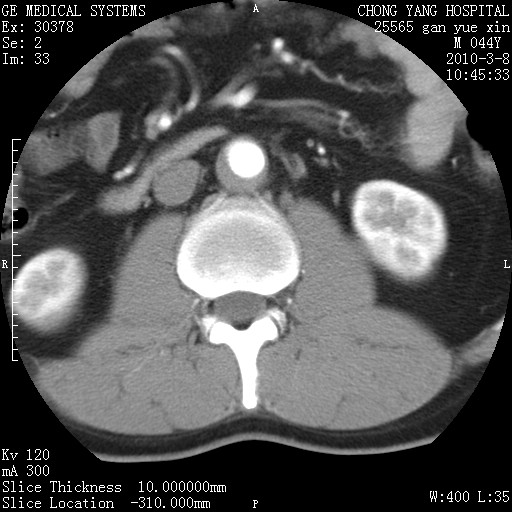

标题: CT24940:主动脉增强,典型病例。 [打印本页]

标题: CT24940:主动脉增强,典型病例。

夹层动脉瘤。

动脉夹层

夹层动脉瘤,典型

主动脉夹层。

动脉夹层的分型:

⒈debakey分型:根据主动脉夹层累及部位,分为三型:ⅰ型:原发破口位于升主动脉或主动脉弓部,夹层累及升主动脉、主动脉弓部、胸主动脉、腹主动脉大部或全部,少数可累及髂动脉。ⅱ型:原发破口位于升主动脉,夹层累及升主动脉,少数可累及部分主动脉弓。ⅲ型:原发破口位于左锁骨下动脉开口远端,根据夹层累及范围又分为ⅲa,ⅲb。ⅲa型:夹层累及胸主动脉。ⅲb型:夹层累及升主动脉、腹主动脉大部或全部。少数可累及髂动脉。

⒉stanford分型:a型:夹层累及升主动脉,无论远端范围如何。b型:夹层累及左锁骨下动脉开口以远的降主动脉。

夹层动脉瘤,少量胸水

夹层动脉瘤;左侧少量胸腔积液。

典型主动脉夹层。